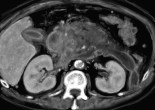

Pancréatite aiguë

La pancréatite aiguë est l’atteinte inflammatoire rapide et potentiellement destructrice du pancréas. On distingue des formes modérées où la régression des symptômes se fait lentement sans séquelles et des formes … Lire la suite